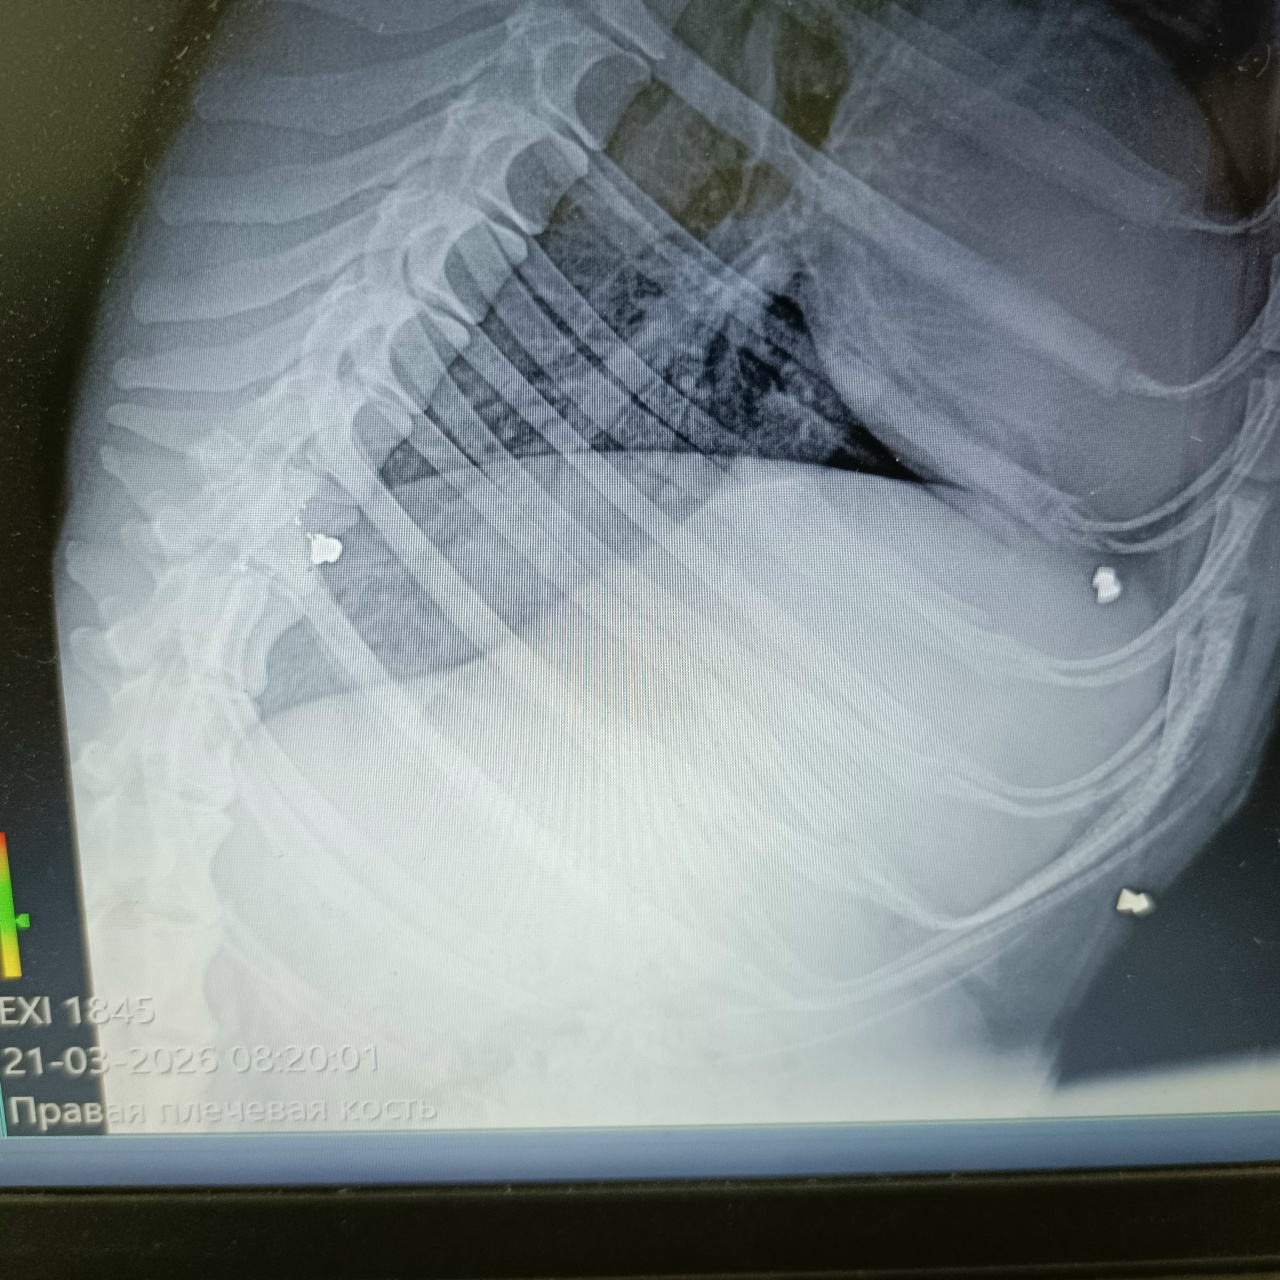

Пёс со множеством пуль в грудной клетке и лапе

По первым фотографиям с места была масса предположений: драка, капкан и даже поезд, но обследование в "Клинике ветеринарной медицины" показало совершенно другую причину.

Пули. Много пуль. В грудной клетке и в лапе.

Но самое печальное, что запястный сустав - разрушен тотально.